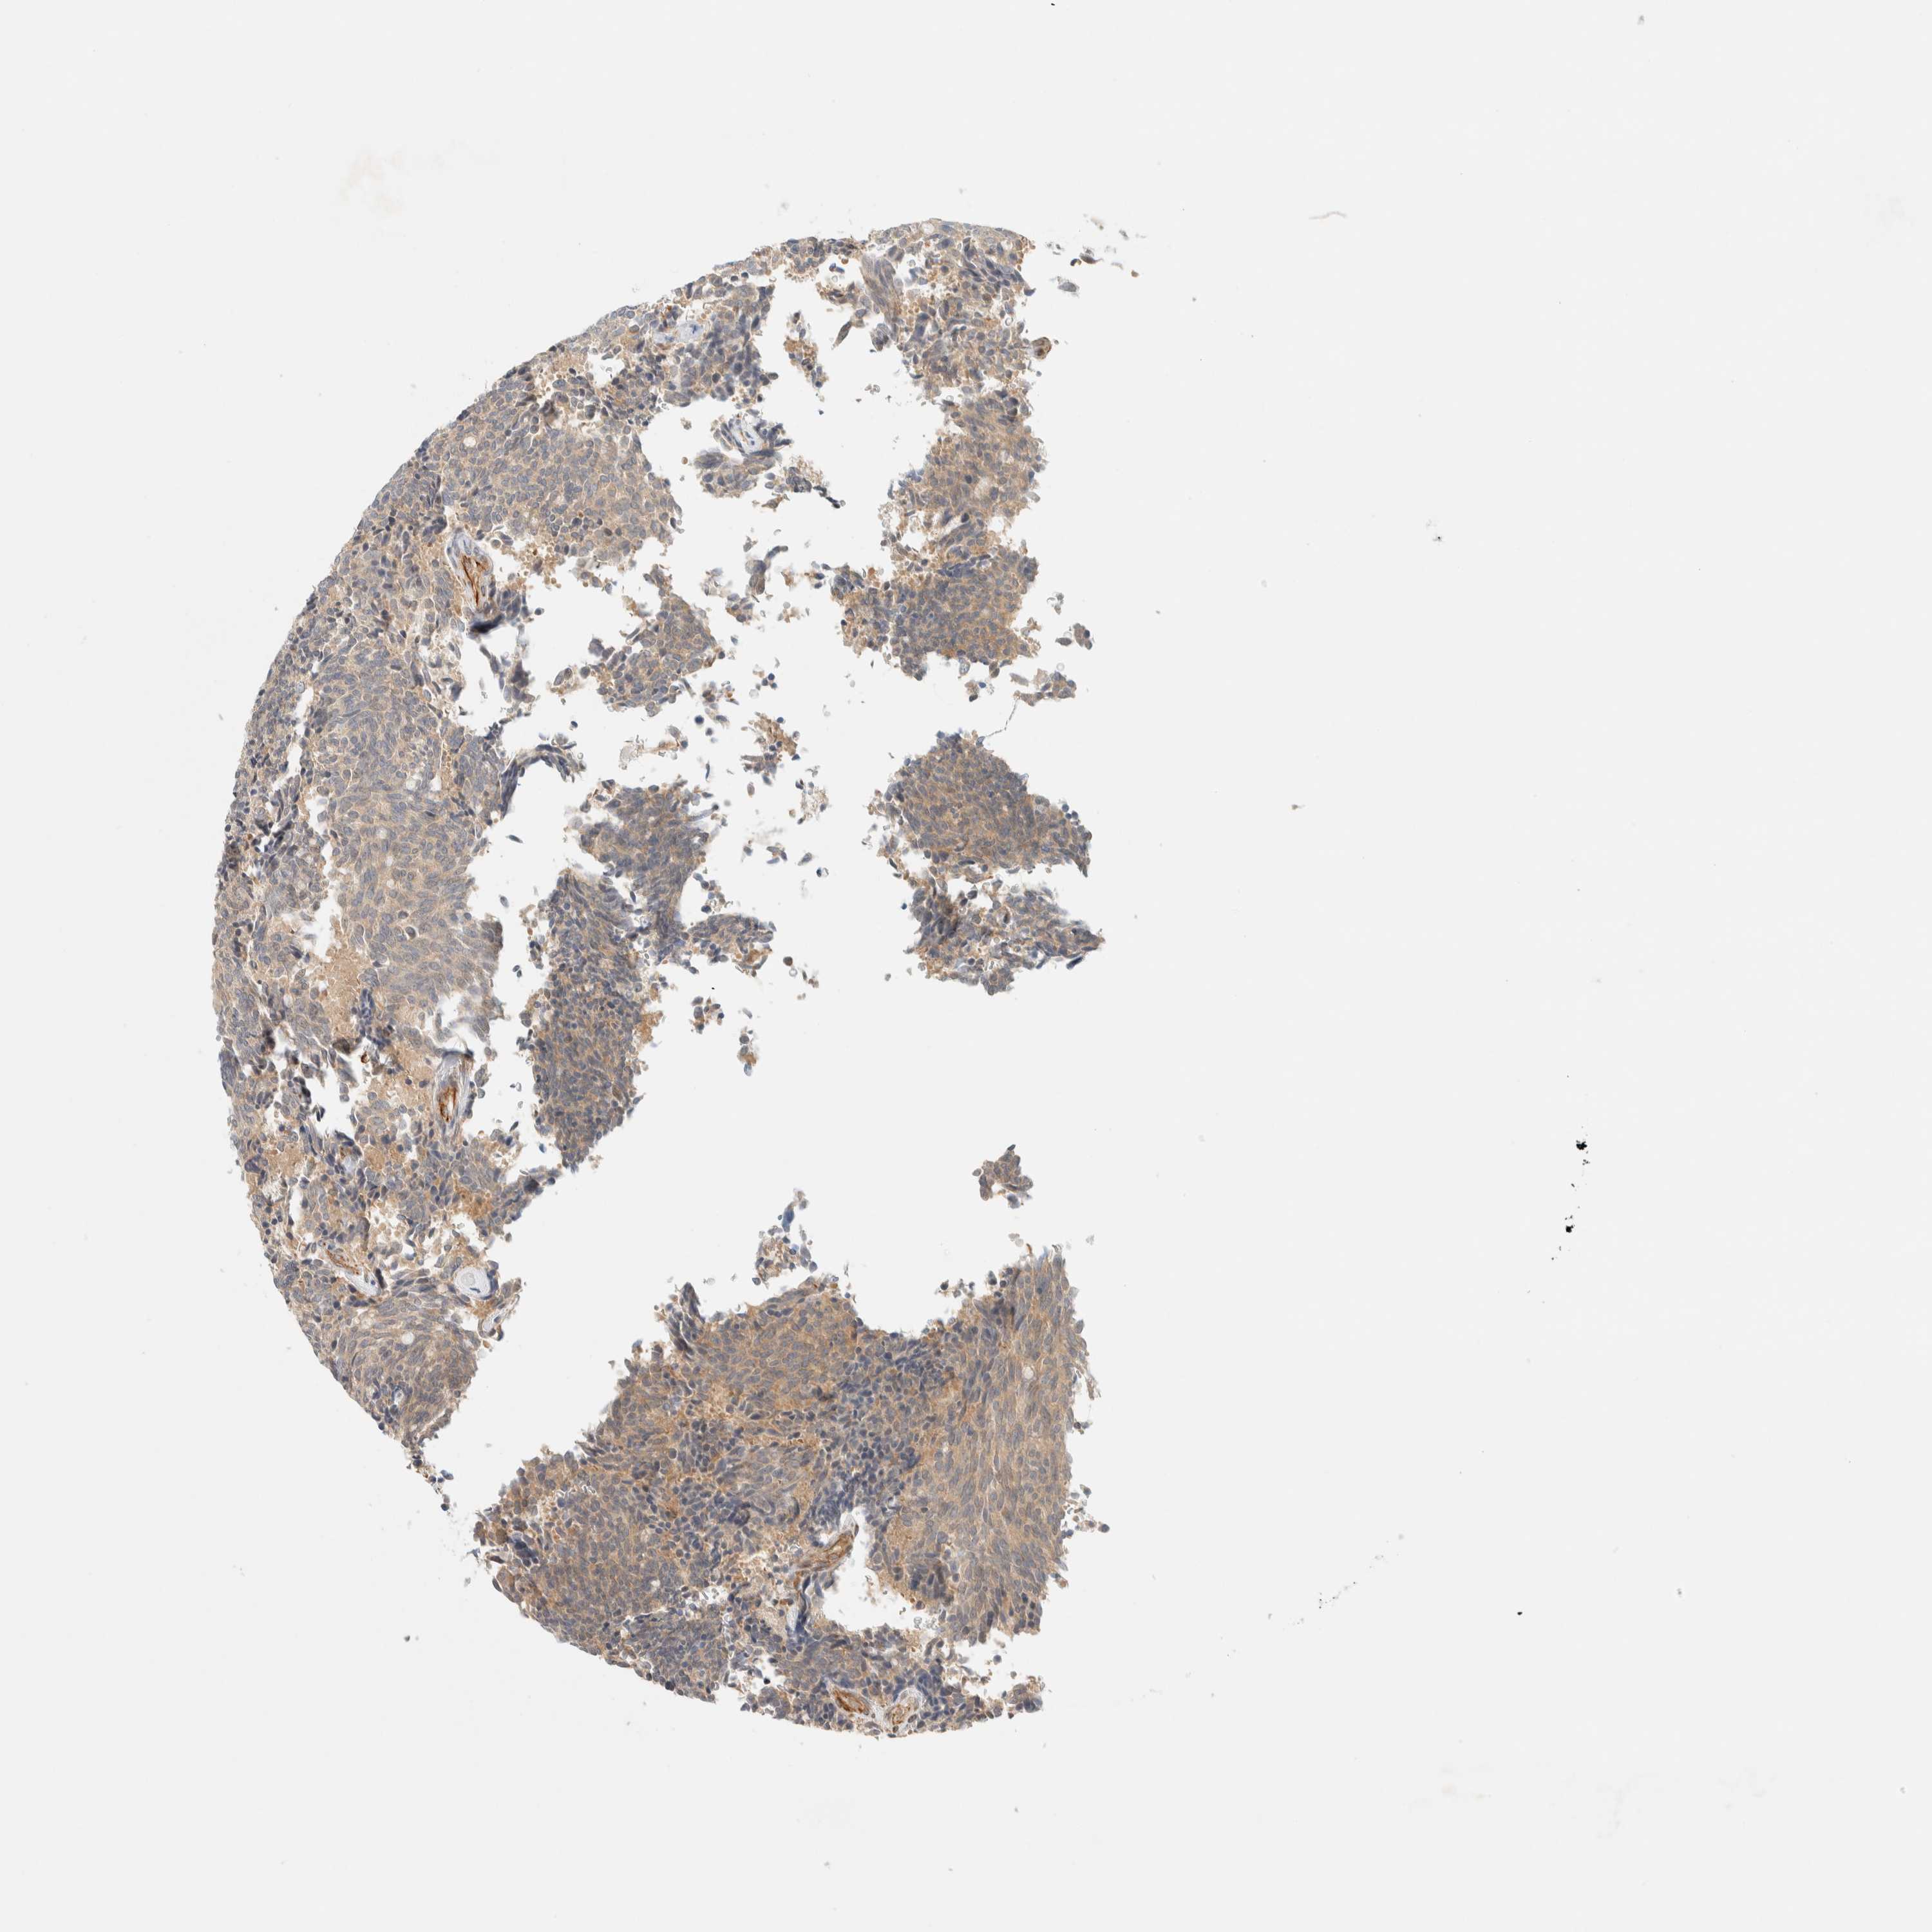

CARCINOID - Protein expressioni

A mouse-over function shows sample information and annotation data. Click on an image to view it in a full screen mode. Samples can be filtered based on level of antibody staining by selecting one or several of the following categories: high, medium, low and not detected. The assay and annotation is described here.

Antibody stainingi

Antibody staining in the annotated cell types in the current human tissue is reported as not detected, low, medium, or high, based on conventional immunohistochemistry profiling in selected tissues. This score is based on the combination of the staining intensity and fraction of stained cells.

Each image is clickable and will lead to virtual microscopy that enables deeper exploration of all samples and also displays staining intensity scores, fraction scores and subcellular localization as well as patient and tissue information for each sample.

Antibody HPA001869

Antibody HPA023882

Staining

High

Medium

Low

Not detected

Intensity

Strong

Moderate

Weak

Negative

Quantity

>75%

75%-25%

<25%

None

Location

Nuclear

Cytoplasmic/membranous

Cytoplasmic/membranous,nuclear

Carcinoid, malignant, NOS

Carcinoma, NOS